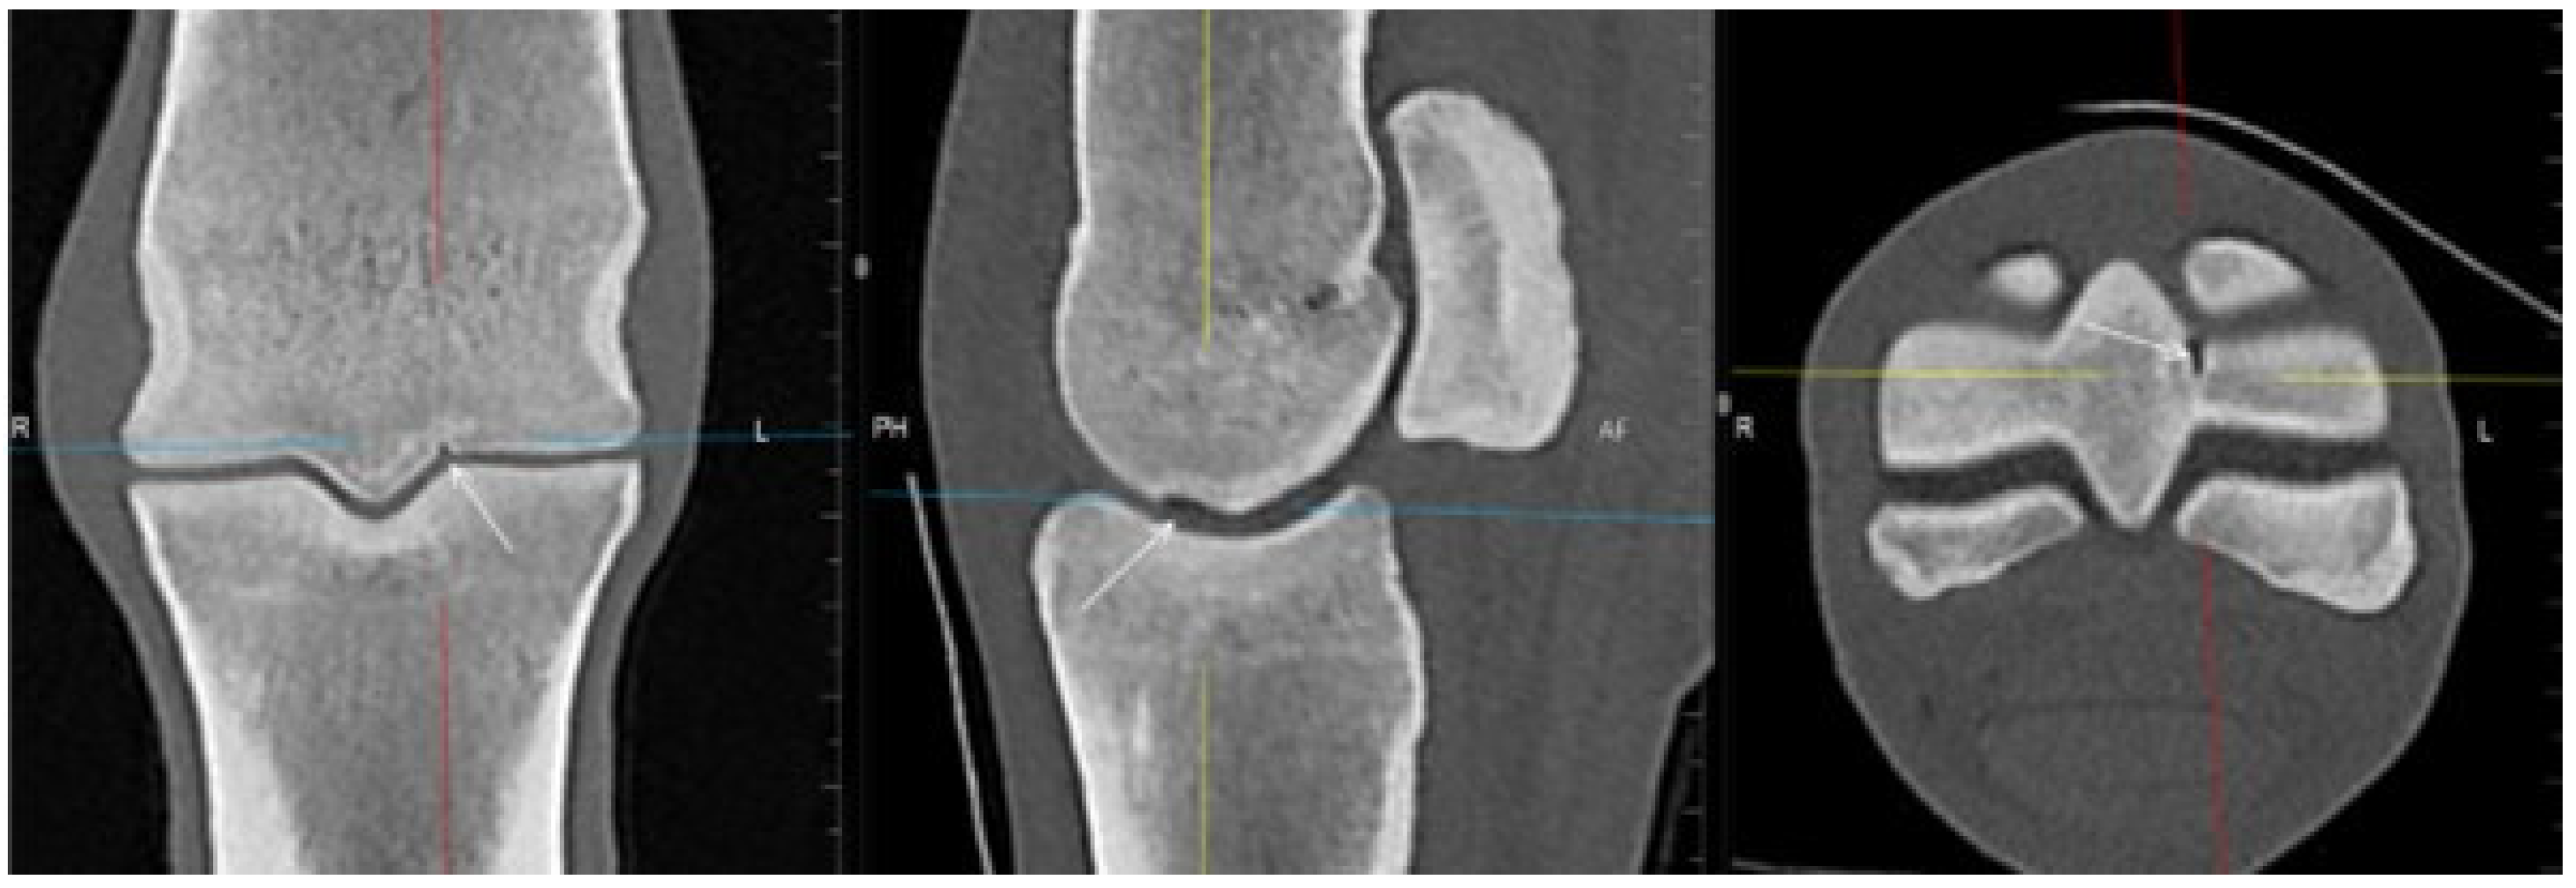

3.2. The Proximal Phalanx

| Proximal phalanx Sagittal groove | |||

| Subchondral bone thickening Dorsal/middle/palmar third Increased attenuation in the trabecular bone Hypoattenuating lesion in the subchondral bone Location | Subchondral bone thickening Dorsal/middle/palmar third Decreased signal intensity in the trabecular bone Increased signal intensity in the subchondral bone Location | Subchondral bone thickening Increased opacity in the trabecular bone Lucent lesion in the subchondral bone Location | |

| Medial/lateral glenoid | |||

| Subchondral bone thickening Dorsal/middle/palmar third Increased attenuation in the trabecular bone Hypoattenuating lesion in the subchondral bone Location Periarticular modelling | Subchondral bone thickening Dorsal/middle/palmar third Decreased signal intensity in the trabecular bone Increased signal intensity in the subchondral bone Location Periarticular modelling | Subchondral bone thickening Increased opacity in the trabecular bone Lucent lesion in the subchondral bone Location Periarticular modelling | |